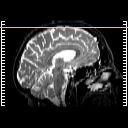

T1-weighted structural MR: Slice 49

Slice 49